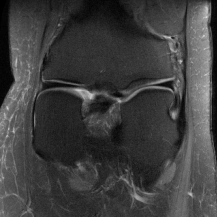

| Ground Truth | Initial | Global | LONDN-MRI | LONDN-MRI | Oracle |

| (1 iteration) | (2 iterations) | ||||

![]() |

| PSNR = dB | PSNR = 19.41 dB | PSNR = 26.52 dB | PSNR = 27.76 dB | PSNR = 27.85 dB | PSNR = 27.92 dB |